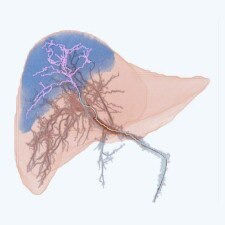

High-resolution images for detailed vision, real-time guidance for accuracy1.

Reduced radiation exposure for both patients and healthcare providers2.

Wide range of interventional procedures for many clinical applications2.

Better performance and optimized procedures for improved patient outcomes1.